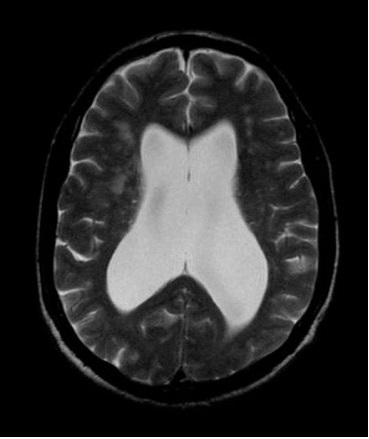

Une chirurgie vous a été proposée. Cette chirurgie a pour but d’évacuer le liquide céphalorachidien (LCR) accumulé dans les ventricules du cerveau vers un autre réservoir (le plus souvent dans le péritoine (ventre)) : dérivation ventriculo-péritonéale. Parfois, le terme shunt peut être employé.